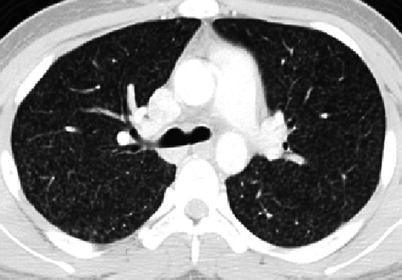

Pulmonary dissemination, usually seen in very young and immunocompromised patients, leads to the formation of pulmonary nodular interstitial granulomas, usually 1–2 mm in size, throughout the lungs. Chest radiographs demonstrate the usual miliary nodular pattern but CT is more sensitive for the detection of miliary TB (Kim et al. 1997) (Fig. 13.21). Adult-type disease presentation is common after primary infection in children over 10 years of age or via endogenous reactivation (postprimary TB) or reinfection. Chest radiograph shows ill-defined, fibronodular parenchymal disease and cavitation mainly involving the apical segments of the upper lobes (Perez-Velez and Marais 2012) (Fig. 13.22).

Fig. 13.21.

Miliary TB. Axial CT image showing small (1–2 mm), uniform nodular densities scattered throughout both lungs compatible with disseminated TB disease